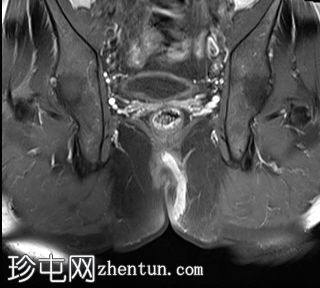

冠状位

T2

位于5点钟和6点钟位置之间,在STIR和T2加权图像上呈高信号。

瘘管起源于括约肌间平面附近,穿过肛门内外括约肌,并延伸至左侧坐骨肛门窝。瘘管内充满液体信号,周围有轻微水肿。肛提肌上方未观察到颅骨延伸。

根据圣詹姆斯大学医院的磁共振分类系统,该病例被归类为III级左侧肛周经括约肌瘘,左侧坐骨肛门窝可见炎症改变。